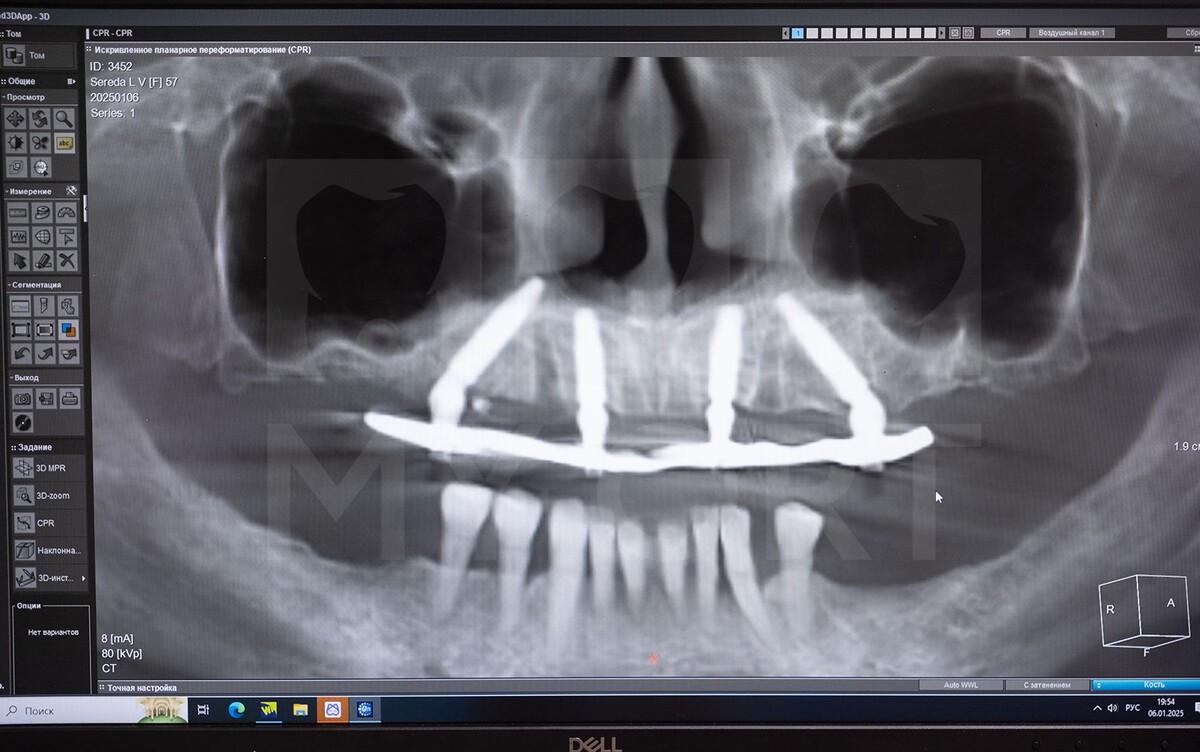

Исходя из собранного анамнеза и результатов компьютерной томографии был отмечен большой генерализованный пародонтоз зубов.

Диагностическое обследование, включая 3D-снимок, показало значительную убыль костной ткани – до 2/3 длины корней зубов. Четыре передних зуба имели выраженную подвижность.

«Удаление и имплантация зубов прошли так же легко, как и в прошлый раз. В этом случае были использованы имплантаты Neodent. Мной сразу же была проведена одномоментная имплантация, на КТ можно увидеть, как хорошо встали имплантаты на нижнюю челюсть. Операция проводилась под наркозом».